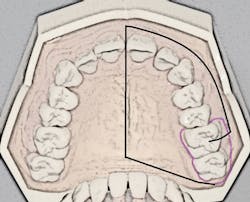

The porous palatal tissue and bone allow penetration of the anesthetic to the dental plexus of the ASA and MSA nerves (on one side), which provide innervation to pulps of the premolars through incisors and, sometimes, the mesiobuccal root of the first permanent molar. The same-side hard palate and palatal gingiva are also anesthesized (see Figure 1).

Recall that the posterior superior alveolar (PSA) nerve block, with its 95% success rate, anesthetizes the molar teeth and associated buccal soft tissues. The ability to anesthetize an entire maxillary quadrant (hemimaxilla) during NSPT with the AMSA and the user-friendly PSA block combination (see Figure 1) results in a reduction of the total number of injections (two versus four to five) and also a reduction of total volume of anesthetic (1.25 to two cartridges versus two to three cartridges). Patients appreciate the reduced number of penetrations as well as the lack of numbness of the lip and face.